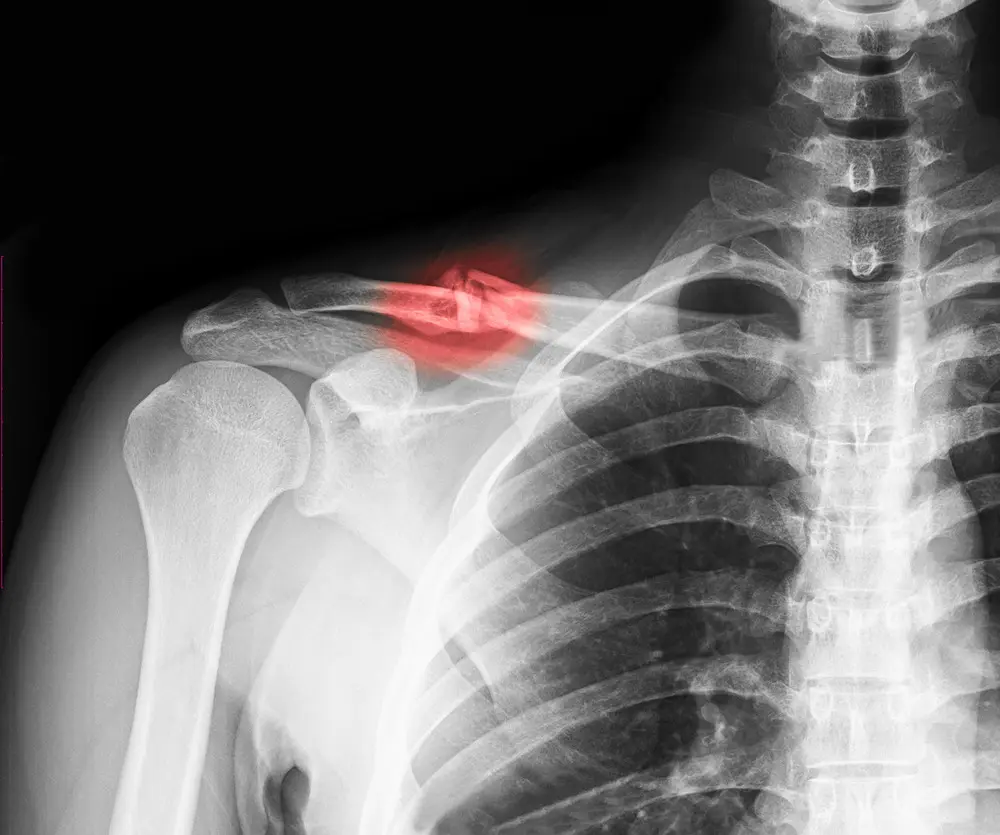

A humerus fracture is a break in the humerus, the long bone of the upper arm that runs from the shoulder to the elbow. This bone plays a key role in arm movement and shoulder and elbow function.

Humerus fractures are commonly classified based on where the break occurs:

• Proximal humerus fracture – near the shoulder joint; often seen in older adults after a fall

• Humeral shaft fracture – occurs in the middle of the bone; commonly caused by direct trauma or accidents

• Distal humerus fracture – near the elbow joint; more common with high-impact injuries

Humerus Fracture